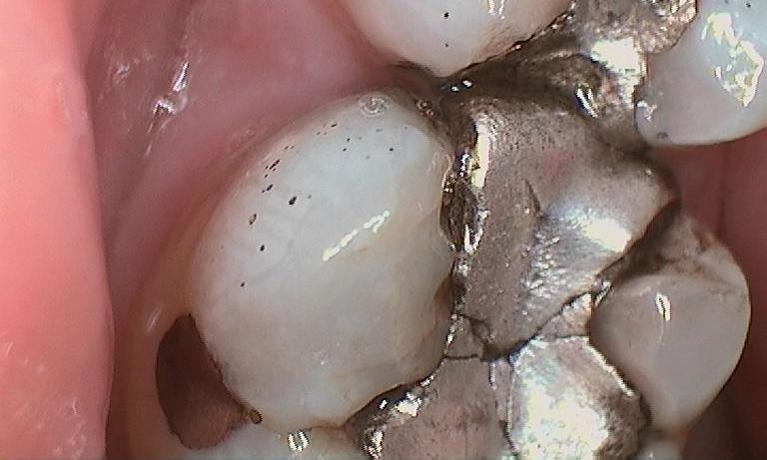

The tooth in the Before photo has a silver filling with quite a few cracks in the tooth. All back teeth have peaks (cusps) and valleys (grooves) allowing to chew your food. Cracks often occur in the valleys of these teeth and around the peaks. These cracks increase the potential for these peaks to break off over time. On this tooth we monitored the cracks and when they began increasing in size, we recommended a crown. A crown (sometimes referred to as a cap) surrounds the tooth 360 degrees. This prevents any part of the tooth or the peaks ...